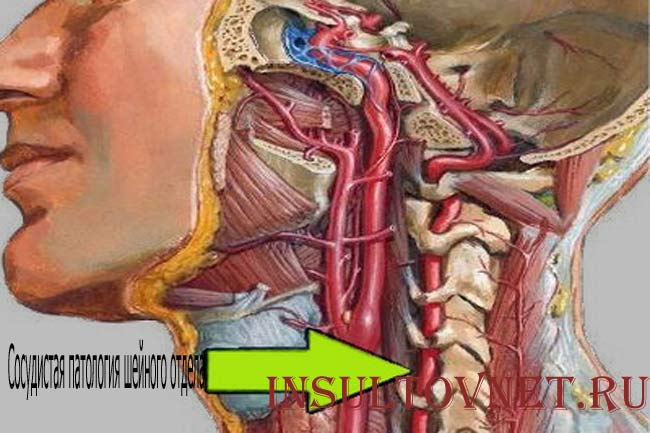

Особенности и диагностика левостороннего кровотока